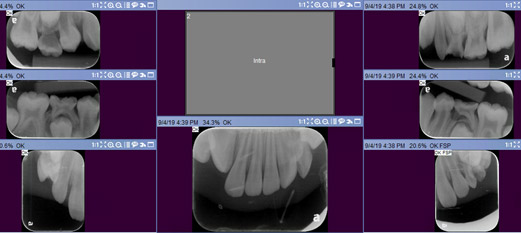

XI. Radiographs

- Radiographs: Based on the American Dental Association guidelines for dental radiograph examinations, selected modified posterior bitewings, occlusals and panoramic were taken to minimize the radiation exposure